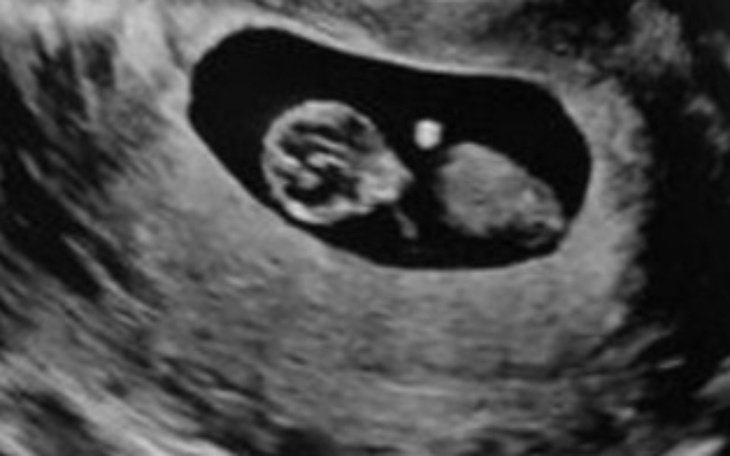

Jestem młodą dziewczyną w ciąży próbuje uzbierać na wymarzone mieszkanie dla mnie oraz dziecka